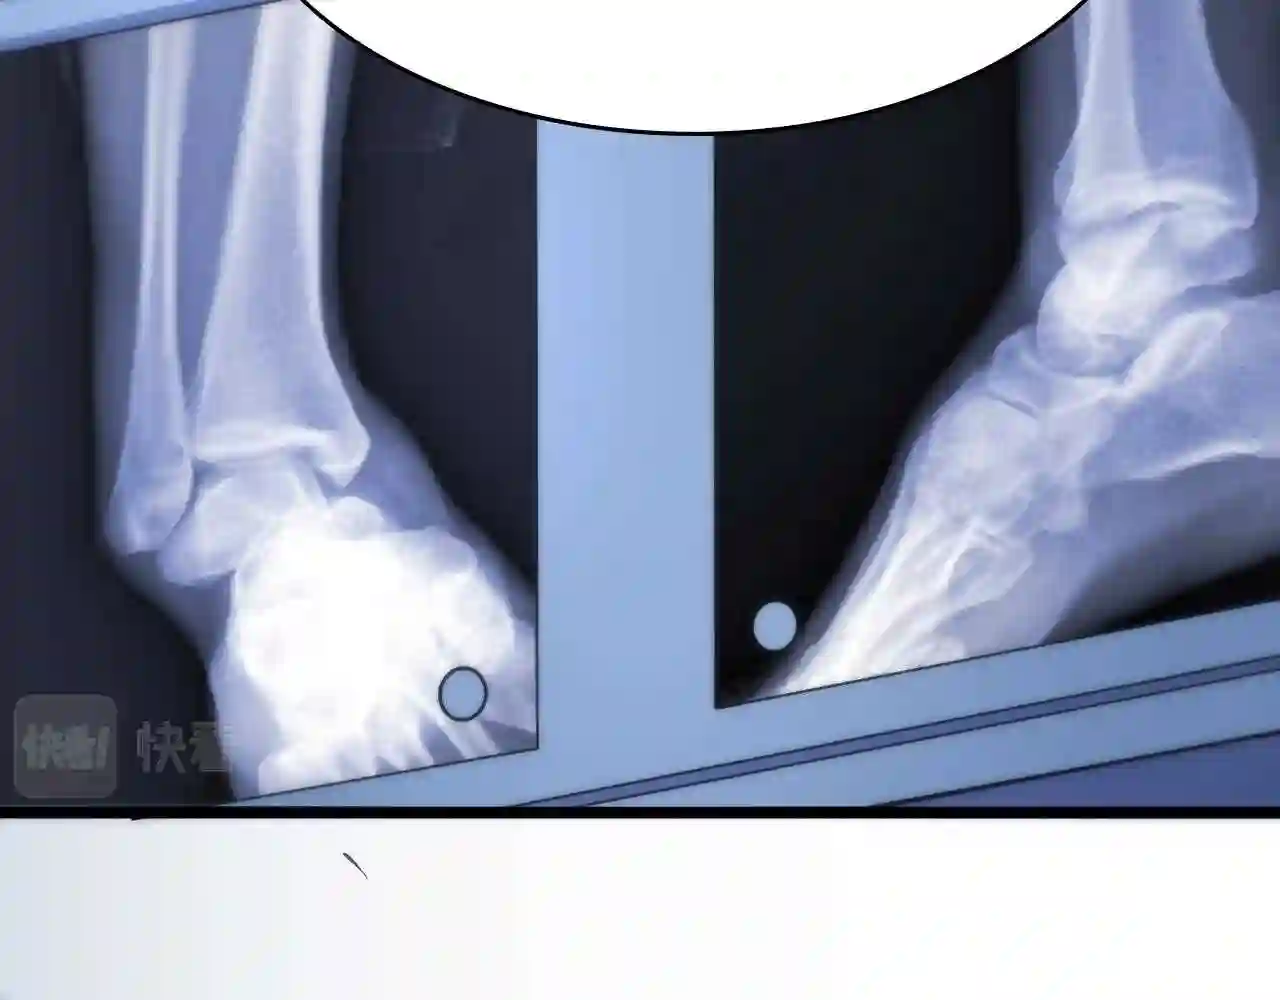

医学生

第64话 拇指缺损再造

本作品讲述了一名医学生从步入医学院到成为一名正式医生的心路历程。